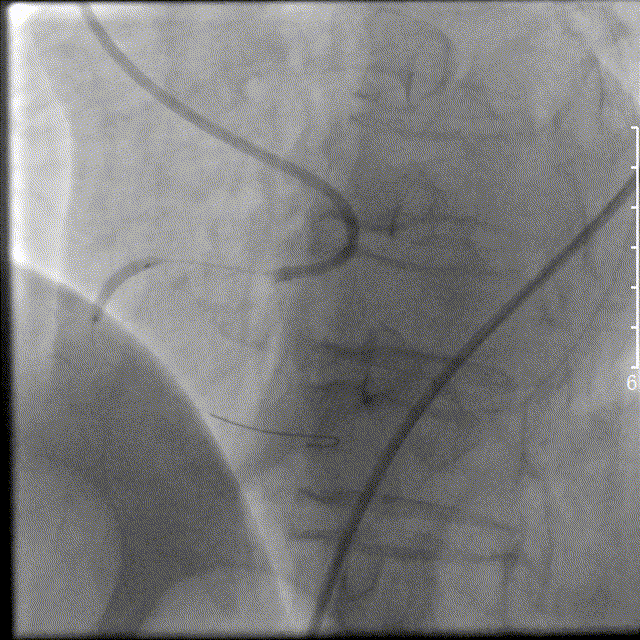

左图:以泰尔茂EXTRACTOR抽吸导管反复进行血栓抽吸。造影见右冠状动脉远段不显影。

右图:将北芯True Reach双腔微导管送至右冠状动脉远段,通过微导管注射替罗非班注射液500ug及硝酸甘油50ug。

右冠远段血流恢复,PDA近段90%局限狭窄,先后以 2.0×20mm球囊及2.5×10mm棘突球囊对后降支近段病变处进行扩张。右冠状动脉血流恢复,血流TIMI3级。术中患者心率慢、血压低,予阿托品注射液0.5mg静脉注射,予去甲肾上腺素持续静脉泵入并间断予间羟胺注射液静脉注射。术后经左侧股动脉行主动脉内球囊反搏。术中共用碘克沙醇90ml。术毕安全送至ICU病房。